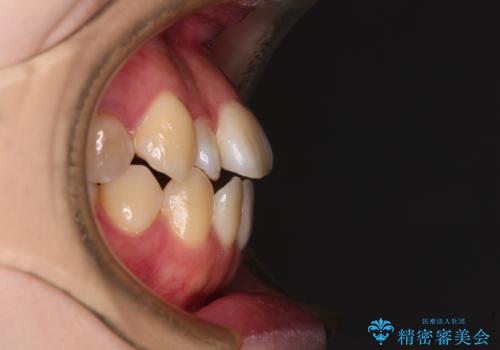

- 上下前歯の隙間を気にして来院された患者様です。

前歯が、舌の突出癖により上下前歯が非接触となっている状態でした。

上下前歯が非接触である開咬は、インビザラインによる治療がお勧めではありますが、しっかりと使う自信がないとのことで、ワイヤー装置にて治療を行うこととしました。